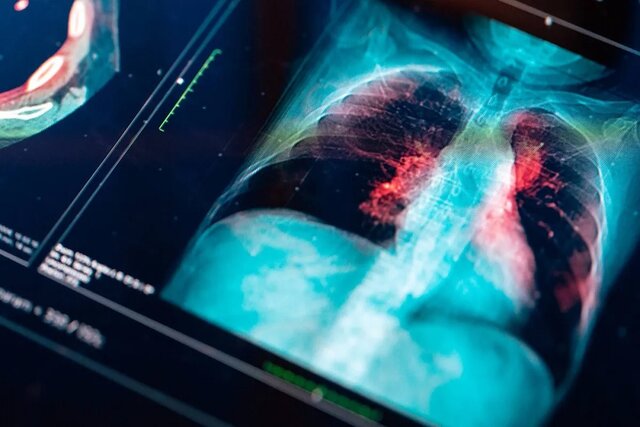

به گزارش ایسنا به نقل از شبکه انبیسی، این بیماری حتی بیشتر از سرطانهای سینه و پروستات جان افراد را میگیرد.

به همین دلیل دستورالعملهای جدید انجمن سرطان آمریکا به میلیونها نفر اجازه میدهد تا اسکنهای معمولی ریه را انجام دهند. بدین ترتیب با تشخیص زودهنگام تومورها، جان انسانهای بسیاری نجات خواهد یافت.

سرطان ریه بسیار کشنده است زیرا بیماری اکثر افراد تا مراحل بسیار پیشرفته، تشخیص داده نمیشوند. بسیاری از سیگاریها و سیگاریهای قدیمی نمیدانند که یک سیتیاسکن ساده باعث میشود سرطان ریه را زود تشخیص و بدین ترتیب جانشان را نجات دهند.